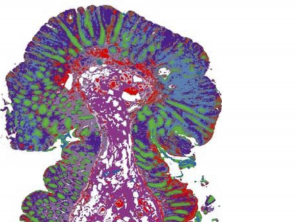

Traditionally, someone in a lab will embed tissue in paraffin, pour dye and view it under a microscope to determine if cancer cells are present. However, researchers in bioengineering and medicine at Carle Health are going further and looking at the microenvironment, or molecular chemistry of the cancer cells to understand cancer progression. By measuring the molecular makeup of cancer cells and their effect on the surrounding cells and tissues, that information can provide insight to patients as to how quickly they need treatment. To accomplish this, they want to build a microscope for a clinical setting to change how to measure and view cells.

Bhargava and Carle Illinois clinical research assistant professor Georgina Cheng, a cancer surgeon at Carle Cancer Institute Urbana, said their research of labeling unique components of the tumor and its cells through

use of infrared-based organizational measurements is predictive of overall survival of colon cancer.

“This is a different way of looking at cancer cells,” Bhargava said. “We asked what is the role of each type of cell in the cancer’s microenvironment and how do the characteristics of each cell relate to the other cells? The spatial organization of those cells are important for prediction of survival for someone with colon cancer, which is one of the deadliest cancers.”